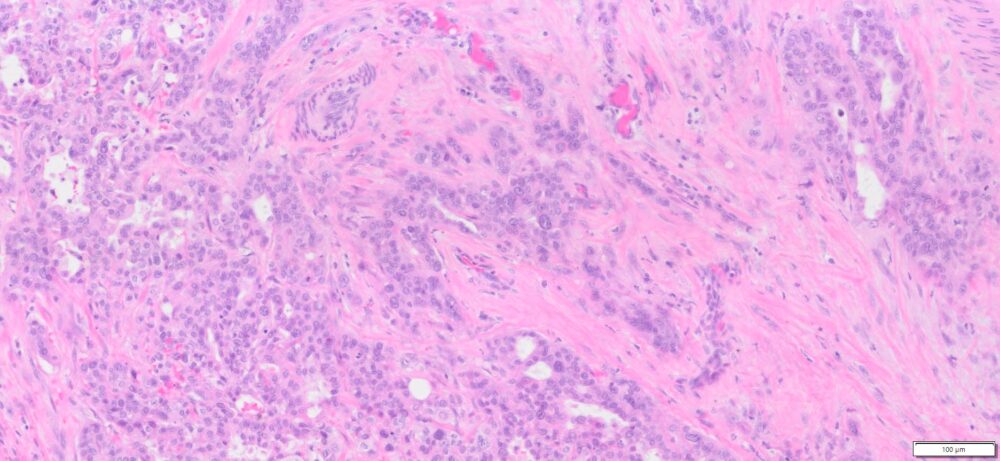

Description

| Tissue | Pathology Diagnosis | Gender/ Age (year) | %Tumor Area | Tumor Grade | TMN/Stage | IHC data |

| Pelvic mass | Human bile duct adenocarcinoma | Female/66 | 30% | II | T3N1M0 | MLH1,2,and6, PMS2 show intact nuclear expression |